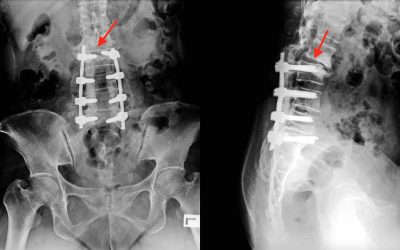

Síndrome del nivel Adyacente o del Segmento Adyacente

El síndrome de nivel adyacente o del segmento adyacente es la complicación más frecuente a largo plazo de una artrodesis vertebral. La artrodesis vertebral es...

Artrodesis lumbar percutánea

La artrodesis lumbar, es decir la fijación de dos o más vértebras sigue siendo la cirugía que más se realiza en la columna. Ya sea cirugía abierta o...